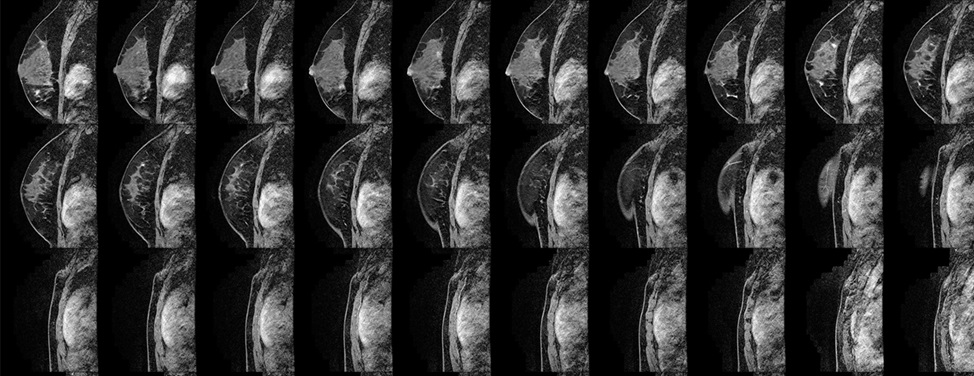

• Breast magnetic resonance imaging (MRI). This type of MRI scan can reveal abnormalities that aren't visible through mammography or ultrasound. Each scan produces hundreds of images.

The American Cancer Society recommends that certain women with an especially high risk of developing breast cancer have an MRI scan along with their yearly mammogram. A breast MRI is noninvasive, with no radiation exposure. But breast MRI is an evolving technology and shouldn't replace standard screening and diagnostic procedures, such as in-clinic exams during a regular checkup, self-exams, mammograms and biopsies.